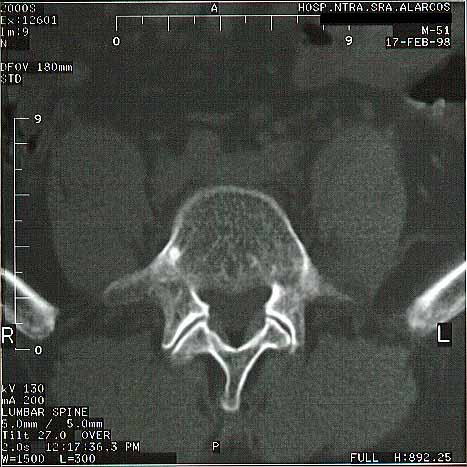

Figura 2.Aplastamientos vertebrales L4-L5.